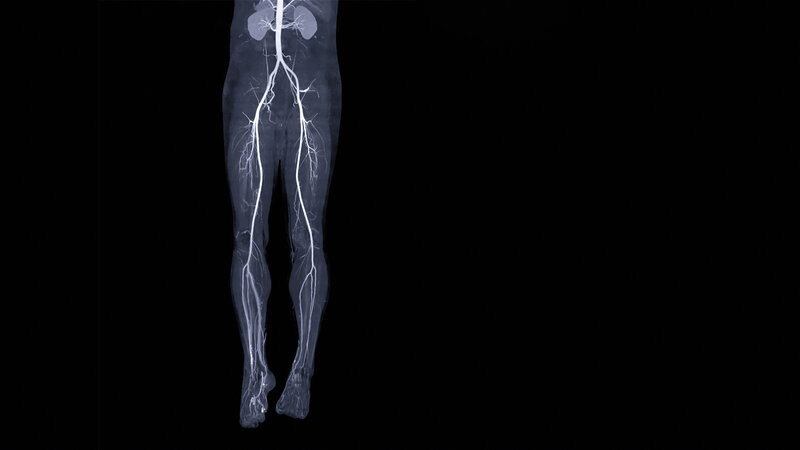

• Rückenlage

• Feet First (mit den Füßen in Richtung Gantry lagern)

• Beine wenn möglich parallel lagern

• Füße parallel lagern und zur besseren Stabilisierung sanft zusammenbinden

• Elevierte Arme (über dem Kopf lagern)